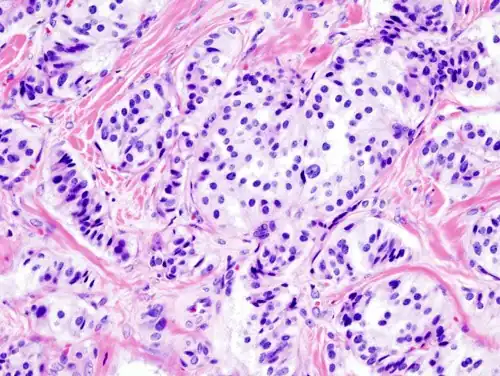

Pathology of pancreatic endocrine tumour (insulinoma). | |